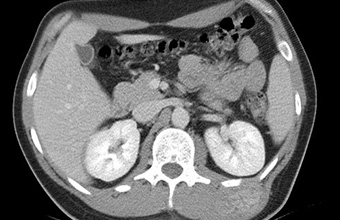

MR u onkologiji

MR u onkologiji poseban je program snimanja bez kojeg je danas nezamislivo rano otkrivanje različitih tumora, raka, nadzor odgovarajućih terapija i kontrola oporavka nakon složenih operacija.